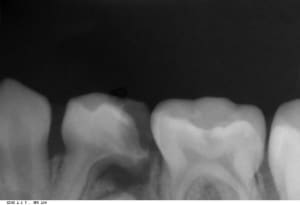

06112015_185222_wfe2jn.jpg